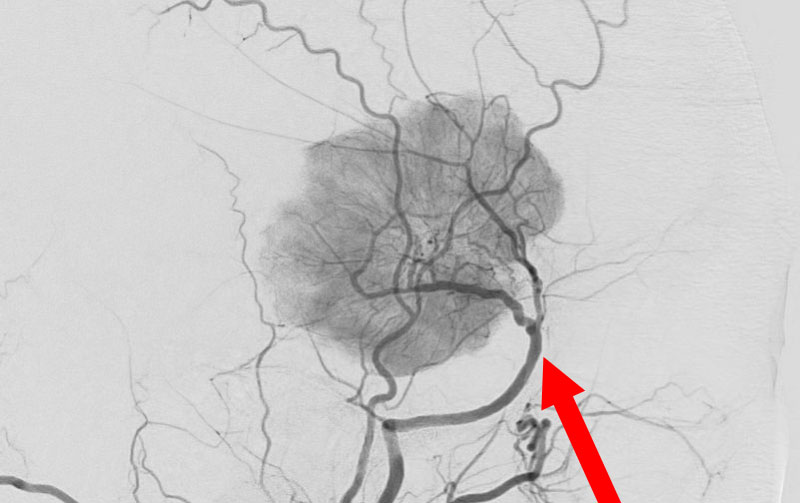

1598

'25年11月26日

右円蓋部髄膜腫

40代

大阪府の病院

手術写真

治療

前